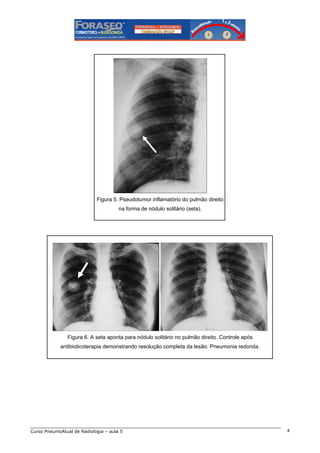

Figura 5. Pseudotumor inflamatório do pulmão direito

na forma de nódulo solitário (seta).

Figura 6. A seta aponta para nódulo solitário no pulmão direito. Controle após

antibioticoterapia demonstrando resolução completa da lesão. Pneumonia redonda.